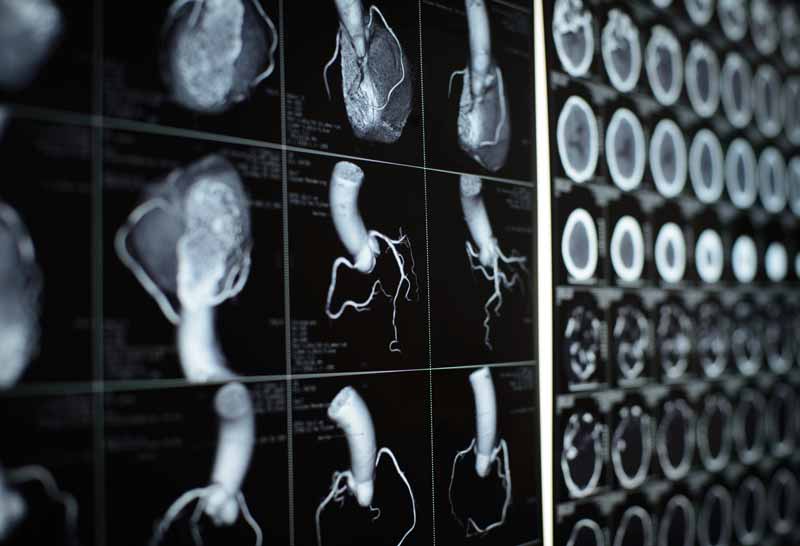

Cardiac CT / CCS

The EncaptureMD Cardiac CT app creates cardiac and coronary anatomy reports using our Visual Coronary Report tool. Draw the vessels and lesions on the diagram and the report is constructed. No need to dictate. Both the diagrams and the text along with procedural data regarding scanner settings is provided.